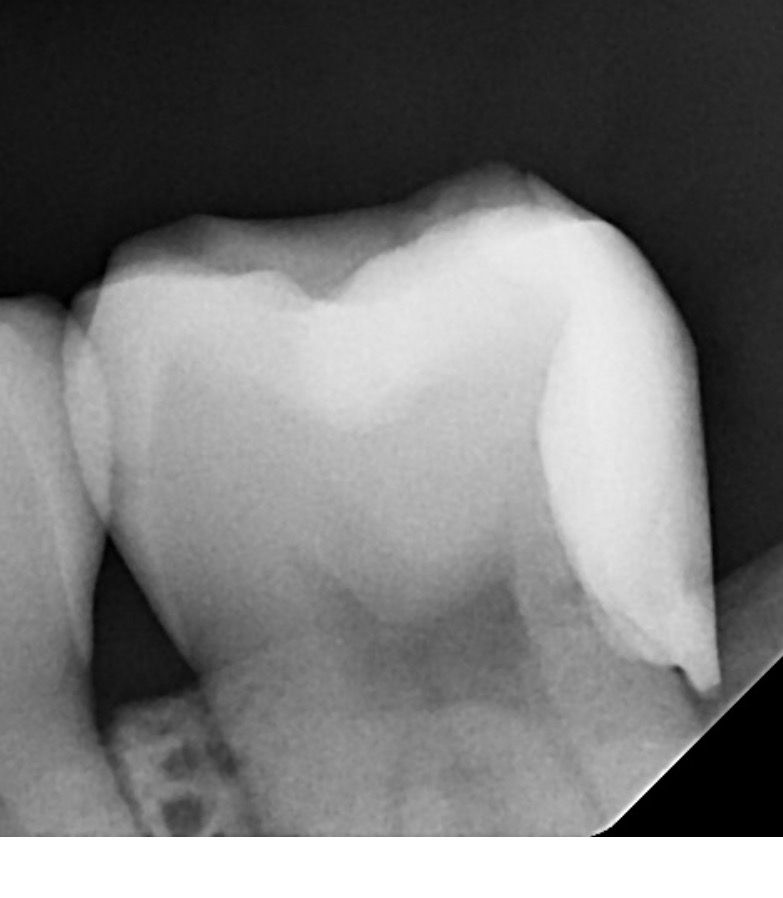

치아 치료한지 좀 됐는데 교체해야 할까요??

안녕하세요, 4년 전쯤 치료한 치아인데 레진이나 복합물 수명이 4-5년이라고 들어서, 선생님들이 엑스레이 보시기엔 괜찮은지 궁금합니다.

크게 아프거나 불편하지 않다면 그냥 사용하셔도 될것같습니다. 엑스레이상으로도 크게 문제가 잇어 보이는건 없습니다.

사진으로 봤을 때 뒤에 있는 수복물의 면이 떠 있는 것으로 보입니다. 치아의 뒷면은 치료하기가 힘든 면이기 때문에 치료를 한다고 해도 완전한 접합이 어려운 경우가 있습니다.

이런 경우에는 레진이라는 치료보다 크라운이라는 보철 치료를 하는 것이 더 좋을 수 있습니다. 경기 부위가 떠 있으면 해당 부위에 이물질이 남아 있게 되고 충치 등이 진행될 수 있기 때문입니다.